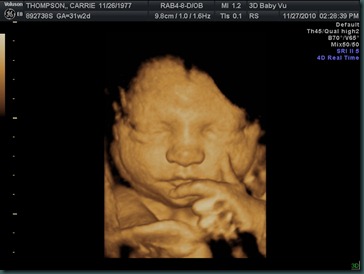

He’s A Thinker Already : )

Here’s our little boy thinking in the womb.  We went to a 4D ultrasound yesterday and got to see lots of pictures of him.  He must be thinking “how do I get out of here?”  because he’s a week ahead of schedule.  We can’t wait to meet him and welcome another sweet boy into our family!